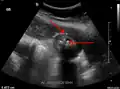

Right upper quadrant abdominal ultrasound is most commonly used to diagnose cholecystitis.[1][26][27] Ultrasound findings suggestive of acute cholecystitis include gallstones, pericholecystic fluid (fluid surrounding the gallbladder), gallbladder wall thickening (wall thickness over 3 mm),[28] dilation of the bile duct, and sonographic Murphy's sign.[13] Given its higher sensitivity, hepatic iminodiacetic acid (HIDA) scan can be used if ultrasound is not diagnostic.[13][14] CT scan may also be used if complications such as perforation or gangrene are suspected.[14]

Abdominal ultrasonography showing gallstones, wall thickening and fluid around the gall bladder

Acute cholecystitis as seen on ultrasound. The closed arrow points to gallbladder wall thickening. Open arrow points to stones in the GB

Acute cholecystitis with gallbladder wall thickening, a large gallstone, and a large gallbladder- Significant gallbladder wall thickening[29]